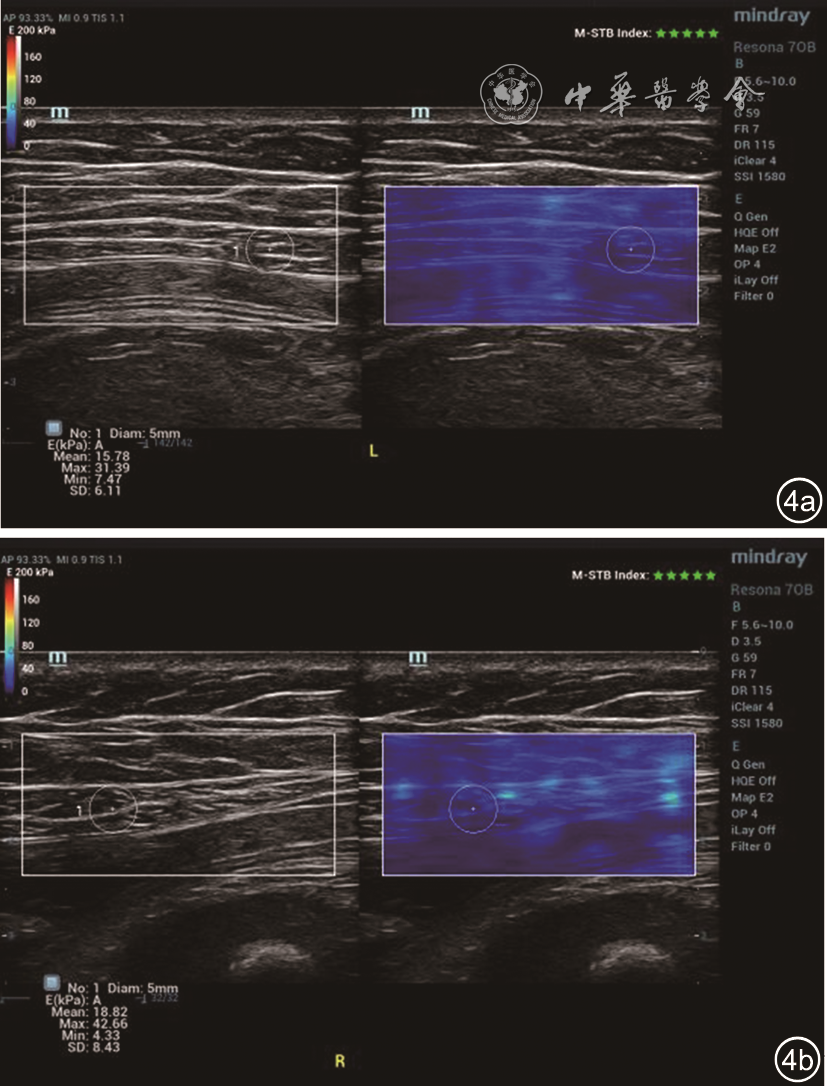

图4 28岁初产妇妊娠37+3周,脐上5 cm水平左侧腹直肌剪切波弹性成像(SWE)参数:Emean=15.78 kPa,Emax=31.39 kPa,Emin=7.47 kPa(图a);右侧腹直肌SWE参数:Emean=18.82 kPa,Emax=42.66 kPa,Emin=4.32 kPa(图b)